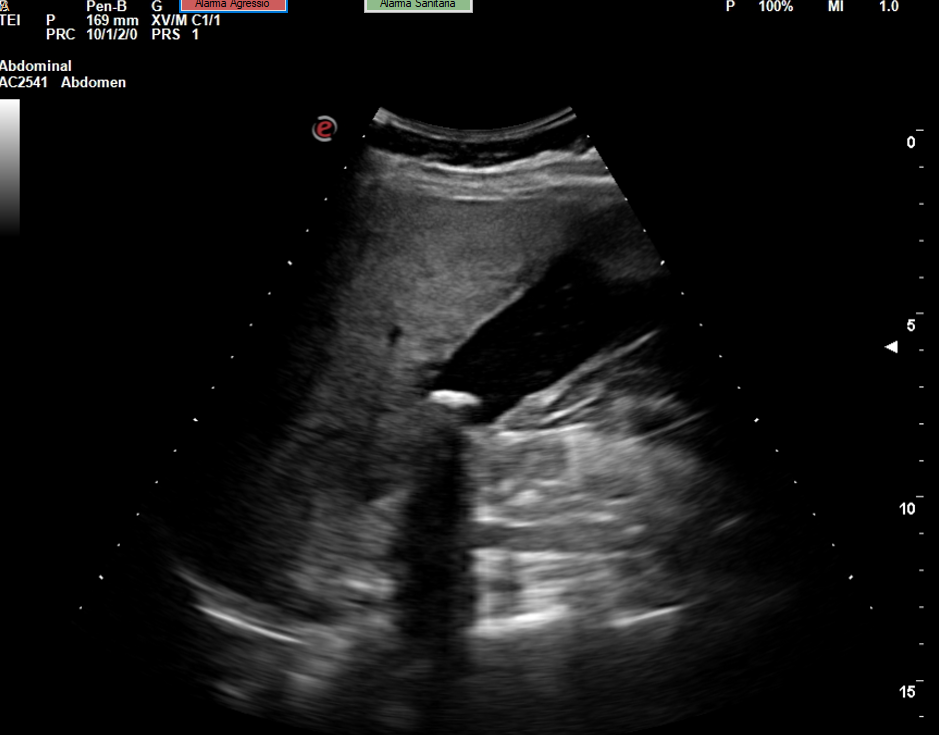

Se realiza la ecografía abdominal en el ambulatorio, donde se objetiva colelitiasis con el colédoco en el límite superior de la normalidad (4,4 mm), también presenta esteatosis hepática grado I. El resto de la ecografía no presenta hallazgos de interés.

Colelitiasis con colédoco en el límite de la normalidad.